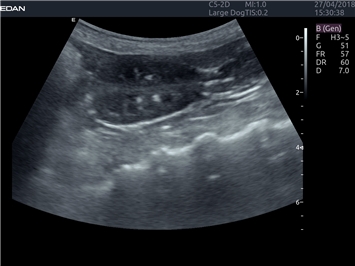

EDAN Acclarix LX4 VET представляет собой профессиональную ультразвуковую систему, специально разработанную для ветеринарных исследований. Сочетание стабильности, высокой производительности и эффективности делает эту систему идеальным выбором для современной ветеринарной практики.

• Оптимизация изображения для различных видов животных

• Улучшенная детализация структур

• Универсальные датчики для различных видов животных

• Специализированные предустановки для ветеринарных исследований